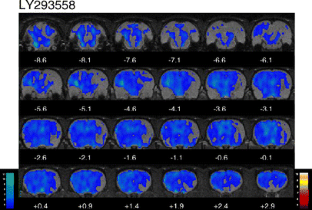

LY404187 produced significant increases in BOLD contrast in brain regions including the hippocampus, lateral and medial habenulae and superior and inferior colliculi. These changes were blocked by LY293558. When administered alone, LY293558 caused widespread decreases in BOLD contrast.

Fig. 2

Fig. 3

Fig. 4